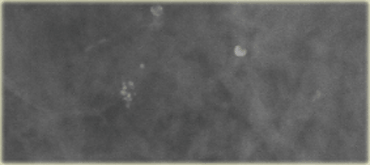

On the left a patient with new calcifications detected in a screening program.

These are fine pleomorphic and fine linear calcifications.

The distribution is linear.

On the basis of the morphology and distribution these calcifications were classified as BI-RADS 4C.

At biopsy this was high grade DCIS.